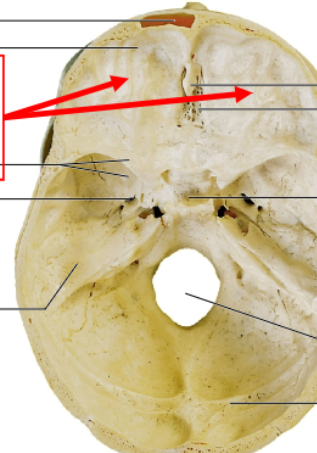

the eyeballs and the muscles that surround them

what would sit under the bone where the red arrows point?

the sphenoid

the most structurally complex and intricate bone of the entire body and is where the sella turcica is